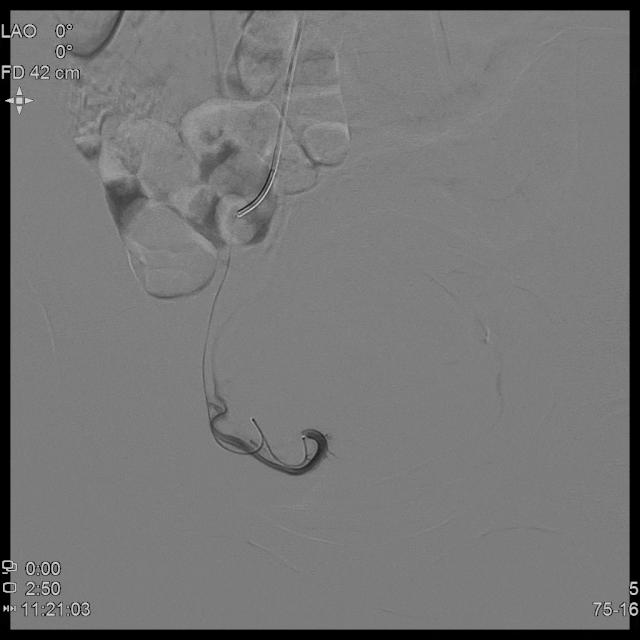

- 经桡动脉入路置入导管造影显示双侧子宫动脉明显增粗,染色丰富,子宫明显增大

- 进一步超选插管右侧子宫动脉造影确认位置